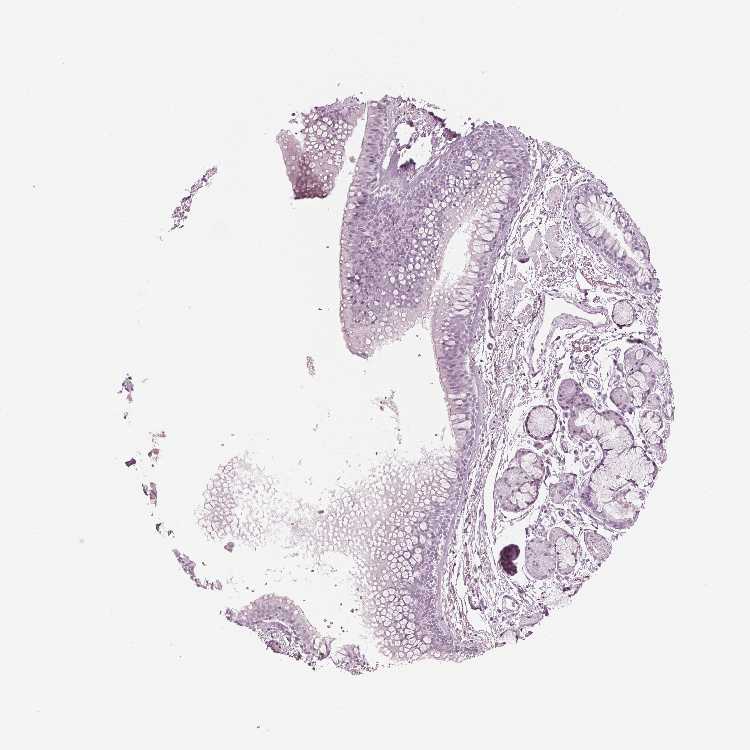

SOFT TISSUE 1 - Antibody stainingi

Antibody staining in the annotated cell types in the current human tissue is reported as not detected, low, medium, or high, based on conventional immunohistochemistry profiling in selected tissues. This score is based on the combination of the staining intensity and fraction of stained cells.

Each image is clickable and will lead to virtual microscopy that enables deeper exploration of all samples and also displays staining intensity scores, fraction scores and subcellular localization as well as patient and tissue information for each sample.

Antibody HPA066890

Fibroblasts Not detected

SOFT TISSUE 2 - Antibody stainingi

Peripheral nerve Not detected